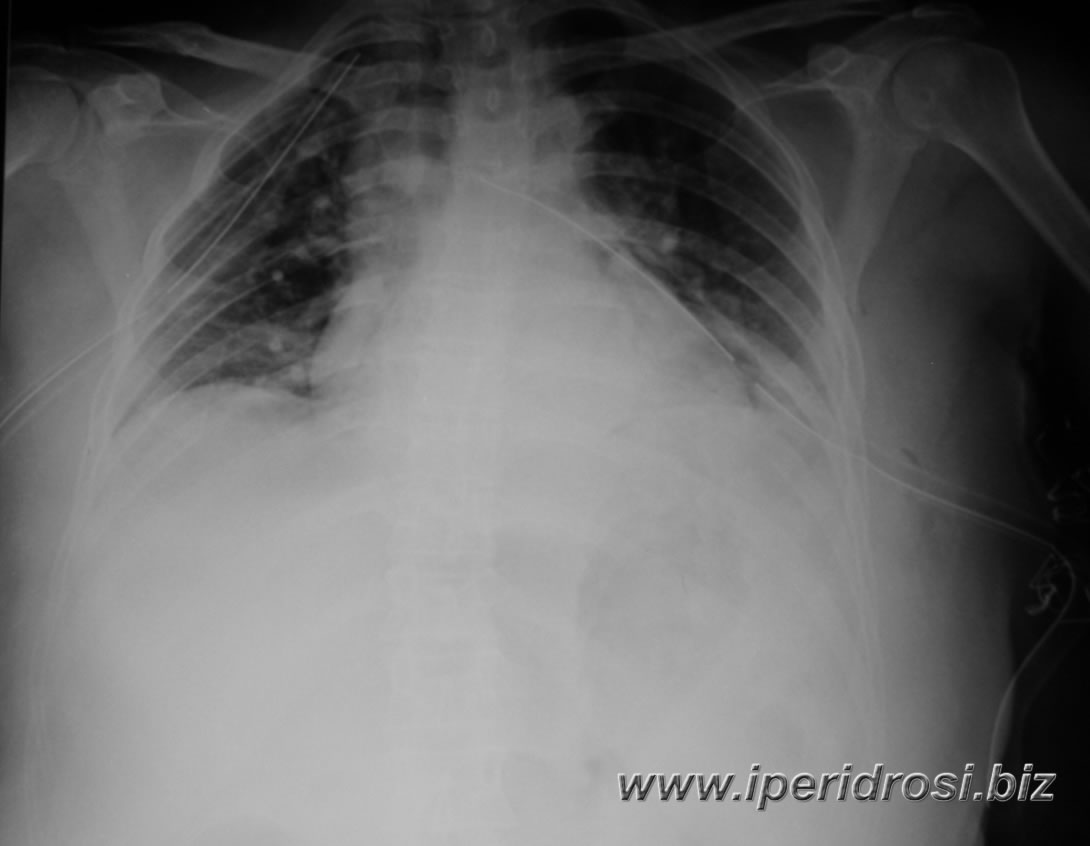

Rx torace ore 18:27 :

quadro invariato.

Rx torace ore 22:48: CVC in VGI dx con apice

sulla proiezione dell'atrio destro. Dal radiogramma eseguito non sono

dimostrabili sicure immagini di falde di pnx. Permangono ad entrambi gli

ambiti polmonari opacità interstizio-alveolari con velatura parietobasale

bilaterale: presenza di tubo endotracheale e drenaggi toracici bilateralmente

(apice del drenaggio a destra che si proietta in corrispondenza del II

spazio intercostale; apice del drenaggio a sinistra in corrispondenza

del V spazio intercostale). |

Rx

torace al letto

ore 09:09 :

opacità parenchimali multiple confuenti su entrambi gli ambiti

polmonari di possibile natura disventilatoria. Polmoni a parete.